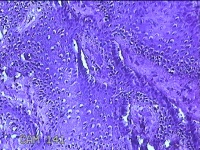

左侧臀部结节

性别

女

年龄

24岁

临床诊断

皮下结节

一般病史

发现左侧臀部结节1年余。

标本名称

大体所见

灰白暗红色带皮肤样结节0.7x0.3x0.2cm一个,表面糜烂,切开结节呈实性,切面灰白暗红色,质软。

图2